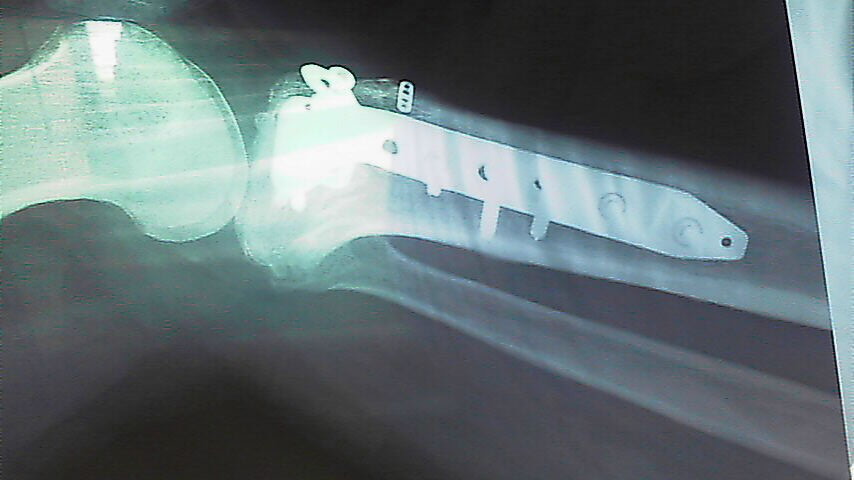

マーニも故障しますが 長い間には体も故障します。 当然オペが必要な場合もあります。 杉さんはマーニも膝も全快しましたが 両膝のオペをしました。そして左の膝は4分割に割れる開放骨折でしたから完治するまでに時間が掛かりました。

膝にプロテクターの入ったクシタニのパンツを穿いていましたが それでも充分ではない場合だってあります。  なので丈夫なプロテクターの装着は必要だなと思うのです。  オペや医療技術は間違いなく向上していますが感染症やその他のリスクを考えると事故などのトラブルは未然に防ぐ事ができればとても幸せです。

手術当時膝に入っていたチタン金具は両手に余る程の量、 金額が30万円ばかりと聞いたそうです。  医療器具なので高価なのですね。  今はこのような話が出来るまでに快復しましたが そうなるまでには誰しも時間が掛かります。

傷跡は かなり派手ですね、 骨折が酷かったので大きく切り開いたのでしょう。

今は医療技術が発達しているので このように再建する事が可能です。 物怖じせずに優秀な医療施設で治療すれば完治できる善い時代になりました。